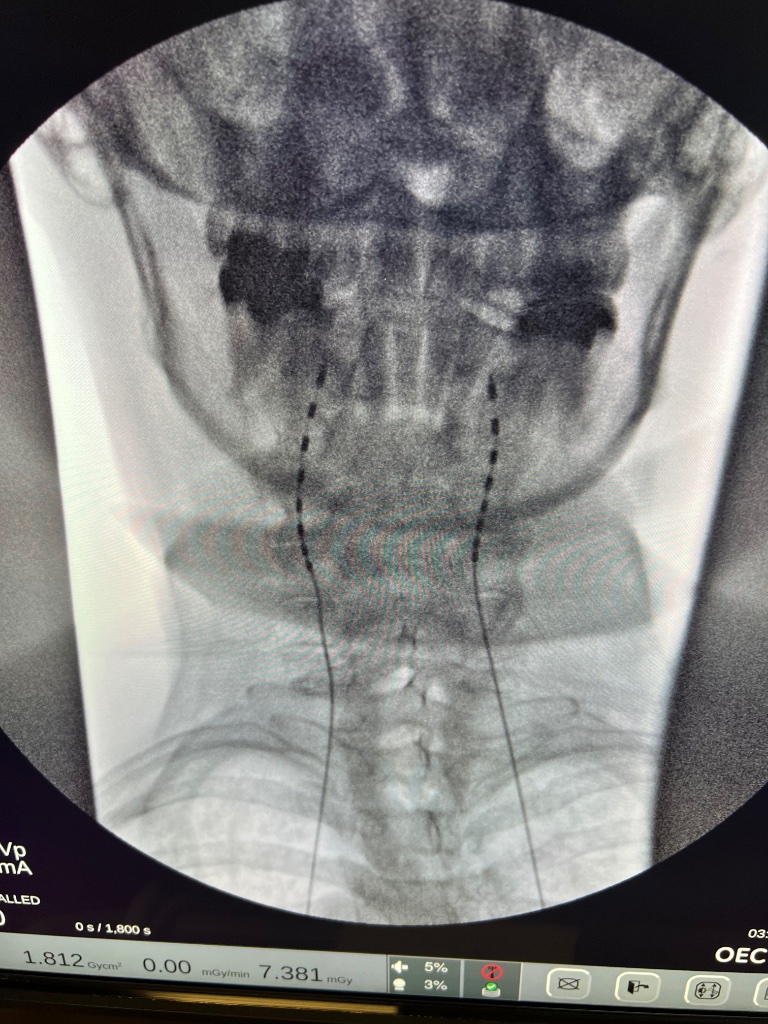

Has anyone here done a peripheral nerve stimulator for Occipital Neuralgia? I have a patient who has done every medical and almost every interventional option for his occipital neuralgia as well as seen tons of academic headache specialists. Nothing has worked. The only thing that has worked are Occipital nerve blocks at the ridge which provide temporary but profound relief (on the order of days to weeks). TON C3/4 Rhizotomies/blocks haven't worked either. So the other day I trialed a PNS stimulator and placed the leads at the bilateral occipital ridges kind of like this picture below (not my actual patient's picture).